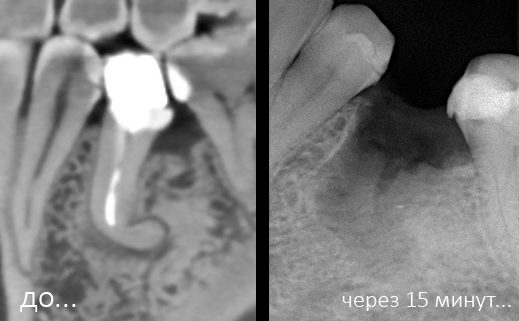

Немедленная имплантация — оптимальное решение в любой клинической ситуации